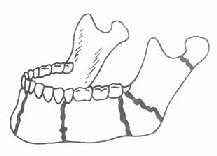

打在上颌骨上可能发生什么骨折呢?

第一型骨折(Lefort Ⅰ型骨折)其骨折线通过梨状孔下缘、上颌窦下部,横行到双侧上颌结节;

第二型骨折(LeFort Ⅱ型骨折)的骨折线通过鼻骨、泪骨、眶底、颧骨下方,达到上颌骨后壁;

第三型骨折(LeFort Ⅲ型骨折)的骨折线也通过鼻骨、泪骨,但横过眶窝及颧骨上方,向后到上颌骨后壁,使上颌骨、颧医学整理骨与颅骨完全分离,因此又称为颅面分离。.